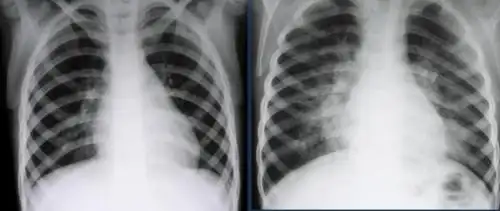

孩子3周岁多点,支气管肺炎入院治疗,6天后,孩子明显好转,医生依然让

请教:6岁,胸片上肺炎,站立位和躺着拍的范围为什么不一样呢